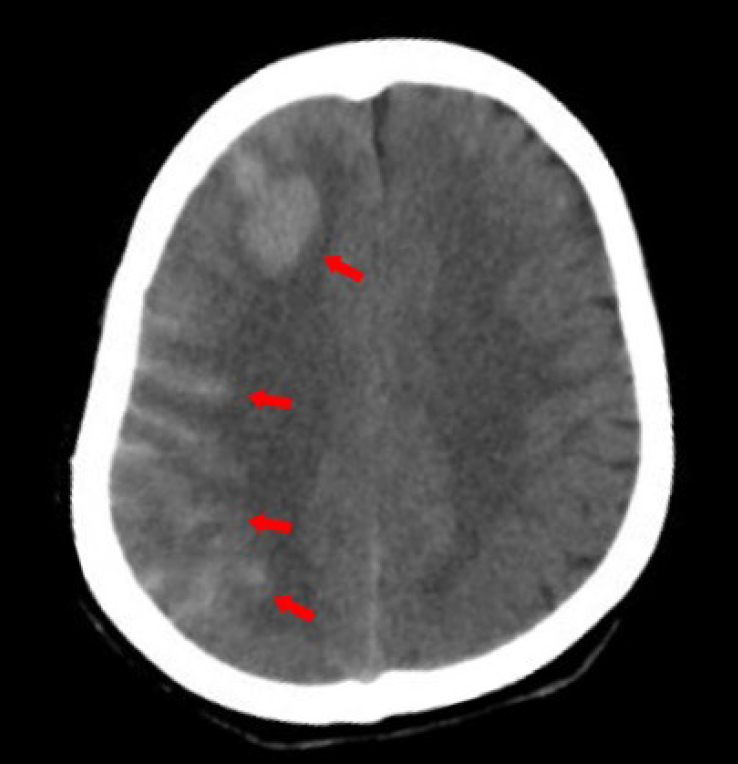

The patient was diagnosed with Takayasu’s arteritis (TAK) and underwent surgery for carotid artery intimal dissection. Following the procedure, the patient experienced a transient loss of consciousness and headache. The computed tomography scan showed subarachnoid hemorrhage in the right frontal lobe (Figure 1). Additionally, the patient suffered an epileptic seizure. Upon discharge, the patient was prescribed aspirin, levetiracetam, prednisolone and methotrexate.

Computed tomography evidence of intracranial hemorrhage after surgery.